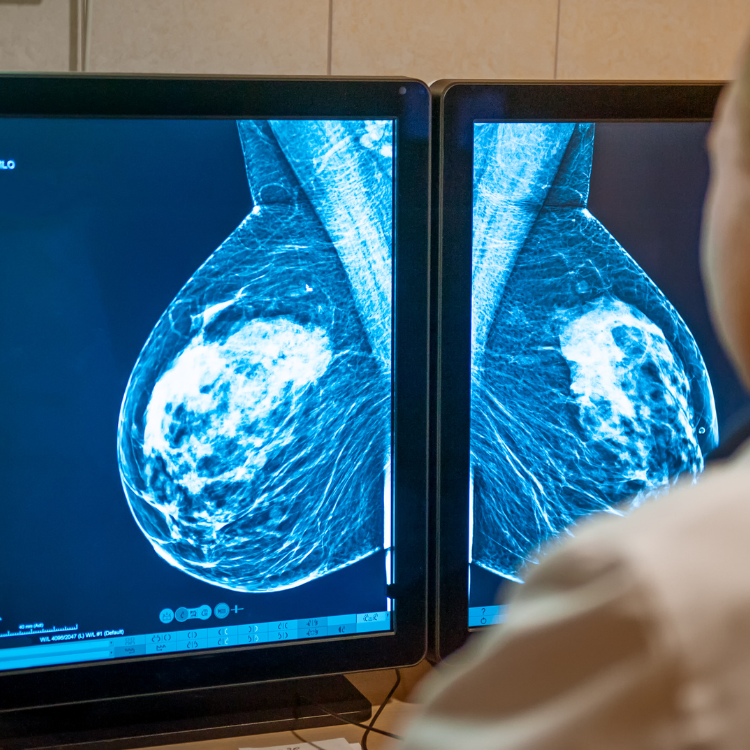

9. Il y a 90 % de chance de guérir si le cancer est détecté à temps.

11. 1,3 million de femmes françaises de 50 à 74 ans n’ont jamais participé à un dépistage, alors qu’il est conseillé de réaliser une mammographie de dépistage tous les 2 ans à partir de 50 ans.